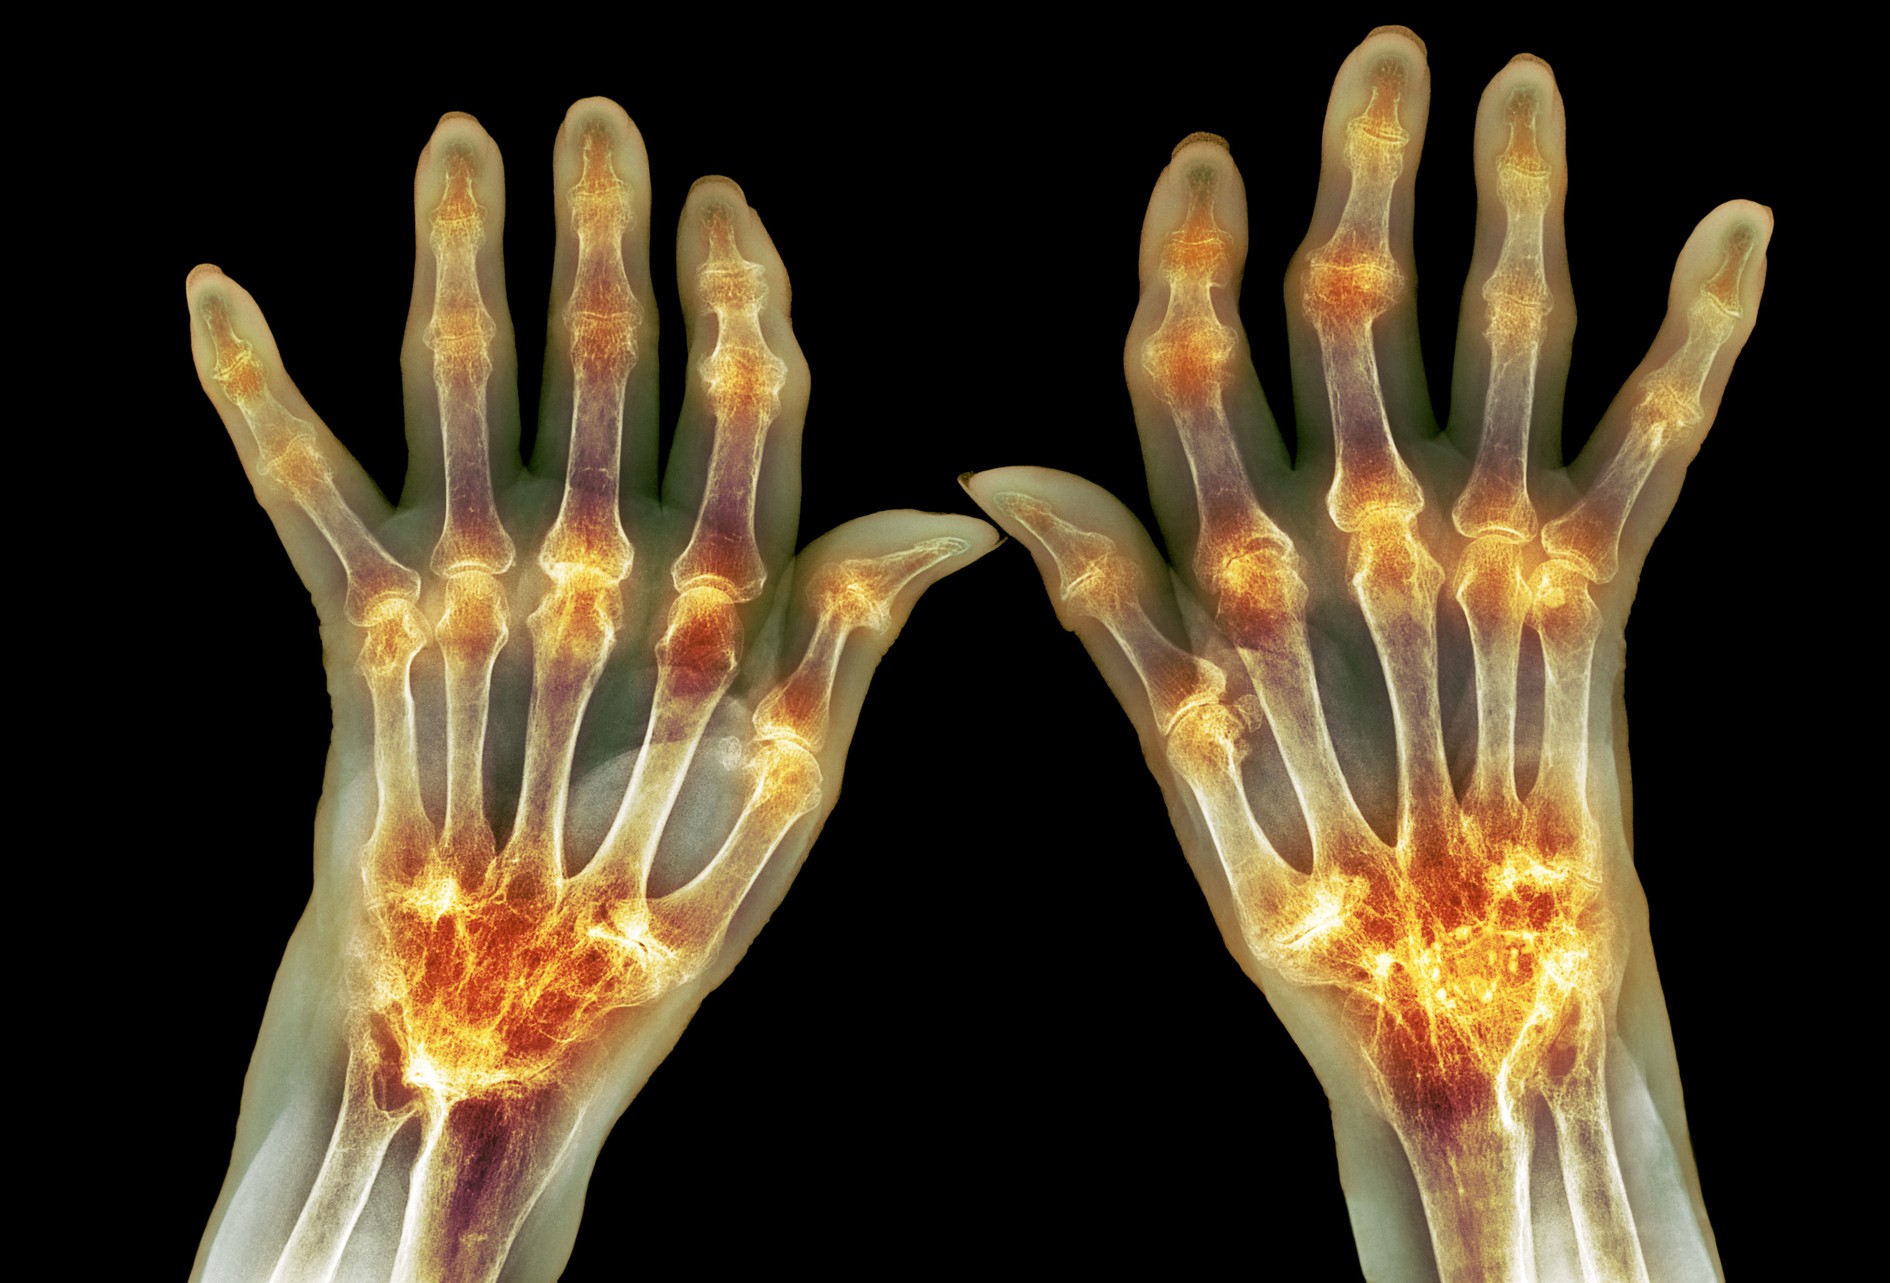

2、類風濕關節(jié)炎

一般中青年女性多見,好發(fā)于手指、手腕等小關節(jié),多為對稱性多關節(jié)炎,有晨僵現象,反復發(fā)作可引起關節(jié)畸形?;烆愶L濕因子及抗CCP抗體等陽性,但血尿酸不高。X線片可見關節(jié)面粗糙和關節(jié)間隙狹窄,晚期可有關節(jié)面融合,但骨質穿鑿樣缺損不如痛風明顯,也無痛風石形成。